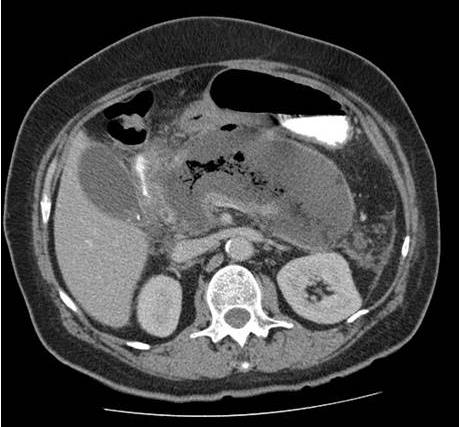

Homem, 48 anos, no nono dia de internação em UTI por quadro de pancreatite aguda necrotizante. No segundo dia, após controle de dor, passou a receber dieta por sonda nasoenteral de forma progressiva e com boa aceitação até o sétimo dia, quando teve recorrência de dor e vômitos, além de três episódios febris em 24 horas e taquicardia sustentada. Atualmente recebendo dieta 1 kcal/mL com volume diário de 1000 mL há dois dias e cinco episódios de vômitos nas últimas 12 horas. Paciente encaminhado hoje para realização de tomografia de abdome com o achado da Figura 11.

Figura 11. Tomografia computadorizada sem contraste de abdome

Tendo em vista a clínica e imagem apresentadas, assinale a alternativa que apresenta qual a hipótese diagnóstica e conduta mais adequada.